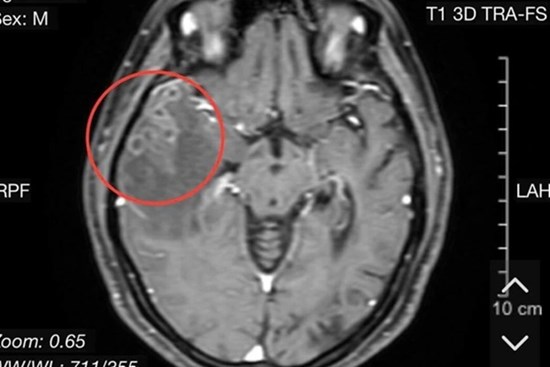

Lại thêm một ca sán làm tổ trong não bệnh nhân

Các y bác sĩ Bệnh viện Hữu nghị Việt Nam - Cuba Đồng Hới Quảng Bình vừa tiếp nhận và điều trị cho một trường hợp người bệnh bị tổn thương viêm não do nang sán.